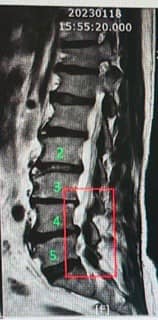

Cervical Spine Treatment Cases 腰椎治療案例 美國開腰椎手術要兩百萬?VS 台灣三週針刀療程的奇蹟 2025.09.23 五年之內歷經三次脊椎大刀之後的醫療反思。 下背手術失敗綜合症候群的一些觀點 脊椎微... 2025.09.22 「脊椎手術有它的價值,但不是每個人都需要大刀──針刀療法給病人多一個選擇」 📌 脊... 2025.09.18 #巨大椎間盤突出一定要開刀嗎? #三家醫院骨科醫師說很嚴重需要手術 #難道真的沒有第... 2025.09.17 ⭕️巨大椎間盤突出,PRP治療失敗、痛到掰咖…他差點走上手術台,卻在這裡看見奇蹟 ⭕️醫... 2025.09.07 【少棒奪冠、脊椎隱憂與台灣棒球的困境】🇹🇼⚾️ 「睽違29 年後的淚水,背後卻有個殘酷... 2025.08.25 ✈️【一張差點被腰痛奪走的法國機票】 ✅一張飛往法國的機票,因為「腰椎管狹窄」而延宕... 2025.08.21 《一碗528元米其林等級牛肉麵的代價》 《脊椎椎間盤巨大脫垂破裂醫案》 「請問還有哪... 2025.08.20 ▶️老人腰痛的真相:骨頭不是第一個壞掉的。 ‼️腰不在骨,根在腸。養脾胃,就是養肌肉... 2025.08.18 【脊椎手術後,還能做針刀嗎?】—— 從筋膜談起的重要四個問題 文/脊椎針刀專門醫... 【足底筋膜痛,竟來自腰椎——多年的疼痛故事】 ✅不是每一個足底痛,都是足底筋膜炎 ... #腰痛別輕忽 #不一定要開刀 #看懂筋膜的語言 #年輕人的腰痛也要重視 #身體健康逆轉勝... 【再次脊椎手術之前,請你聽我說——花蓮陳阿姨的故事】 文/脊椎針刀專門醫師,台灣... 2025.07.30 ✅一年痛到暴瘦十幾公斤,竟然靠六次治療翻轉人生?原本說要開刀,最後成功告別手術。 2025.07.22 ⭕️從超痛到超好:林媽媽的八個月腰劇烈疼痛故事,以及「不用開刀的神經減壓」如何逆轉... ← 上一頁 1 2 3 4 5 下一頁 →